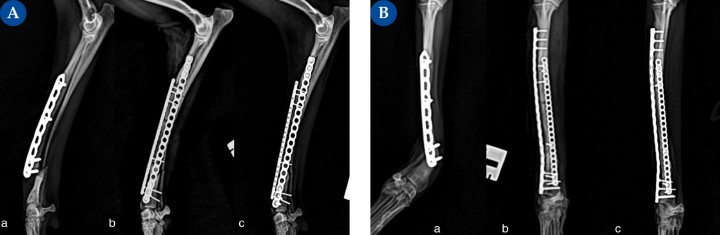

(A) Proyección mediolateral, (B) Proyección craneocaudal. Fractura diafisaria distal de cúbito y radio, oblicua corta, asociada a la colocación de un implante previo, en un paciente lebrel italiano de 2,5 kg.(a) Fractura diafisaria distal de cúbito y radio, oblicua corta. El radio se aprecia esclerótico debido a su anterior intervención, realizada cuatro meses antes. Las reintervenciones de fracturas previamente tratadas suponen un aumento del riesgo de sufrir complicaciones, especialmente a la hora de lograr una correcta cicatrización ósea,<sup>3,7</sup> por lo que se trata mediante un sistema de placas ortogonales.&nbsp;(b) En este caso y por la peculiaridad del radio, más estrecho de lo normal en el plano craneal y más ancho en el plano sagital debido a la cicatrización de su anterior fractura y al efecto del implante previamente colocado, la placa principal se coloca en la cara lateral del radio. Se trata de una placa bloqueada de titanio multiorificio y poliaxial con tres tornillos bloqueados por fragmento, todos de 1,5 mm salvo el más distal, de 2,0 mm (mayor stock óseo). El implante auxiliar se coloca en la cara craneal del radio y se trata de una placa bloqueada de titanio, multiorificio, con dos tornillos bloqueados de 1,2 mm en el fragmento distal y cuatro en el fragmento proximal.(c) Evolución de la consolidación ósea a las 6 semanas postoperatorias.

(A) Proyección mediolateral, (B) Proyección craneocaudal. Fractura diafisaria distal de cúbito y radio, oblicua corta, asociada a la colocación de un implante previo, en un paciente lebrel italiano de 2,5 kg.(a) Fractura diafisaria distal de cúbito y radio, oblicua corta. El radio se aprecia esclerótico debido a su anterior intervención, realizada cuatro meses antes. Las reintervenciones de fracturas previamente tratadas suponen un aumento del riesgo de sufrir complicaciones, especialmente a la hora de lograr una correcta cicatrización ósea,3,7 por lo que se trata mediante un sistema de placas ortogonales. (b) En este caso y por la peculiaridad del radio, más estrecho de lo normal en el plano craneal y más ancho en el plano sagital debido a la cicatrización de su anterior fractura y al efecto del implante previamente colocado, la placa principal se coloca en la cara lateral del radio. Se trata de una placa bloqueada de titanio multiorificio y poliaxial con tres tornillos bloqueados por fragmento, todos de 1,5 mm salvo el más distal, de 2,0 mm (mayor stock óseo). El implante auxiliar se coloca en la cara craneal del radio y se trata de una placa bloqueada de titanio, multiorificio, con dos tornillos bloqueados de 1,2 mm en el fragmento distal y cuatro en el fragmento proximal.(c) Evolución de la consolidación ósea a las 6 semanas postoperatorias.